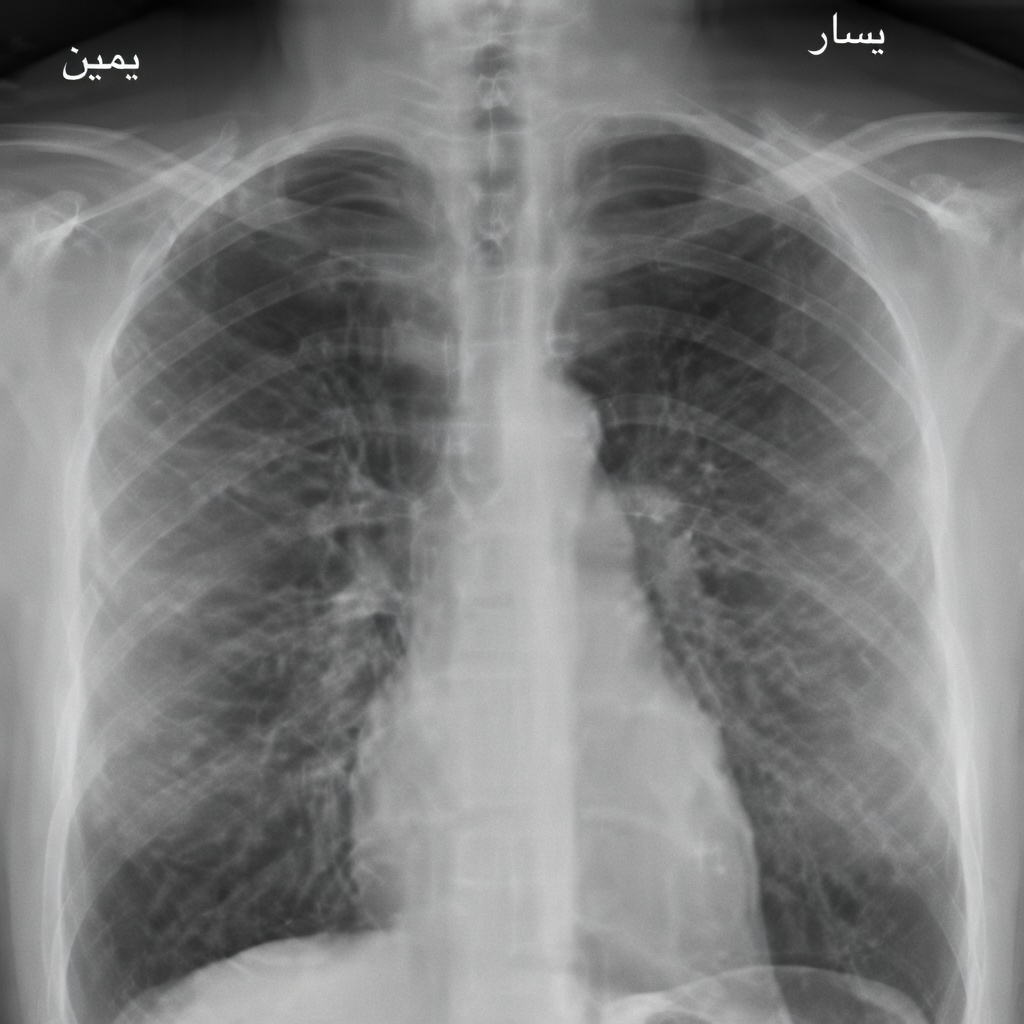

4) أشعة الصدر الروتينية (Chest X-ray): غير مفضّلة لغير المدخنين دون أعراض تنفسية

تُعد أشعة الصدر السنوية أو الروتينية مثالًا كلاسيكيًا على الفحوصات التي يُستحسن تجنّبها لدى الأشخاص غير المدخنين الذين لا يعانون سعالًا مزمنًا أو ضيقًا في التنفس أو أعراضًا رئوية. من سلبياتها:

- تعرض للإشعاع (حتى لو كان أقل من CT)

- احتمال ظهور “اكتشافات عَرَضية” تقود إلى فحوص ومتابعات غير ضرورية

توصي إرشادات متعددة بالاستخدام الموجّه حسب الأعراض أو عوامل الخطورة بدل إجراء أشعة الصدر بشكل تلقائي ضمن الفحص السنوي.